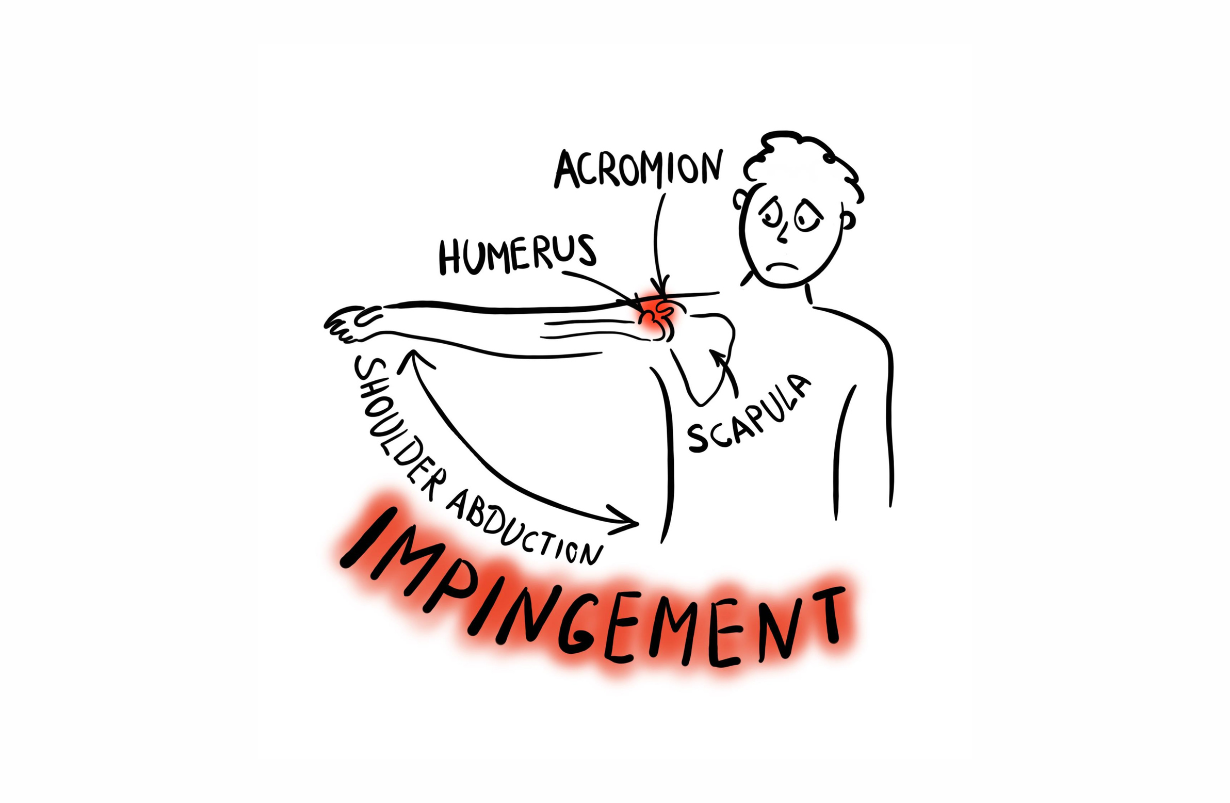

Shoulder Impingement

Non-physiological and painful contact between the humerus (arm bone) and the acromion (highest and most lateral part of the scapula or shoulder blade) that restricts abduction and flexion of the arm. It is generally due to extra bone formation on the lower surface of the acromion which intersects the humerus at 140 -150 degrees, instead of allowing it to abduct and flex closer to 170 - 180 degrees.